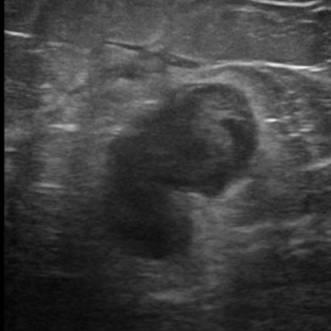

Di căn vú

» Thông tin: Nữ giới – 70 tuổi.

» Lâm sàng: Khối tuyến vú / K hắc tố.